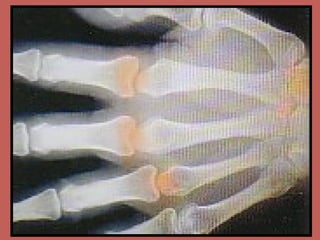

Opioid Receptor Brain Distribution